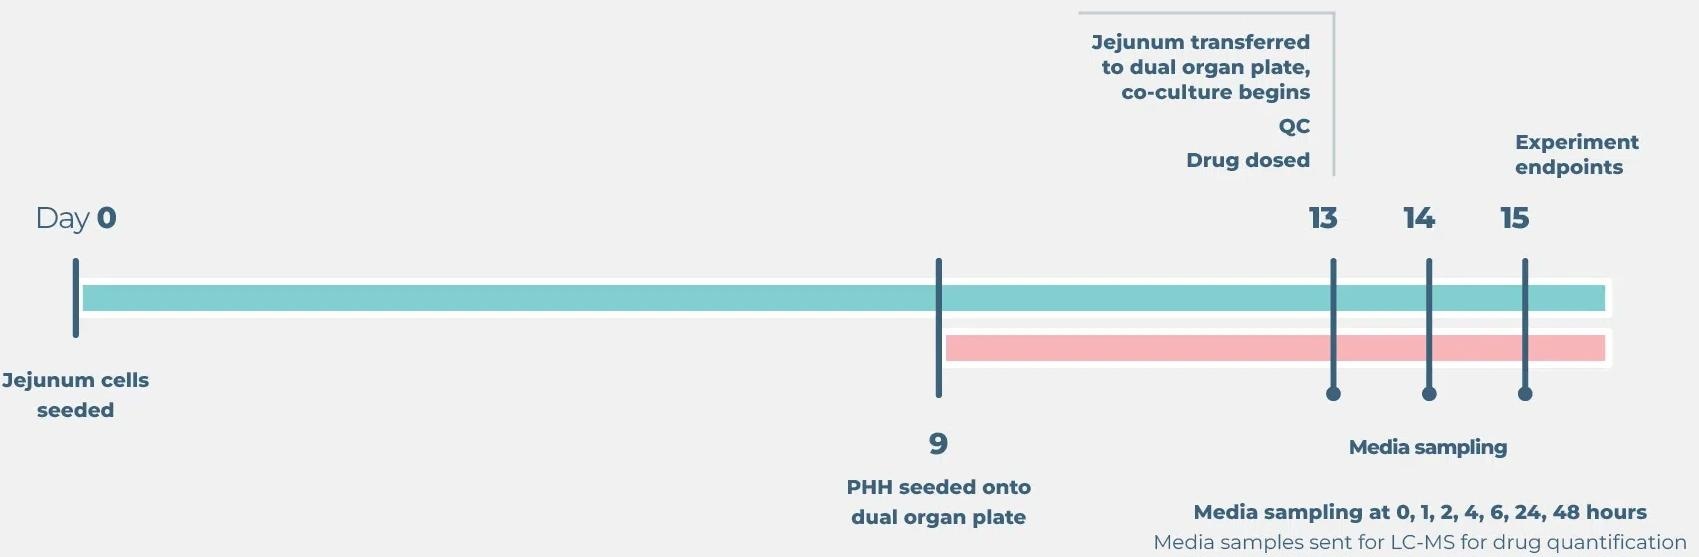

Standard gut/liver drug bioavailability cell culture timeline

Image Credit: CN-Bio